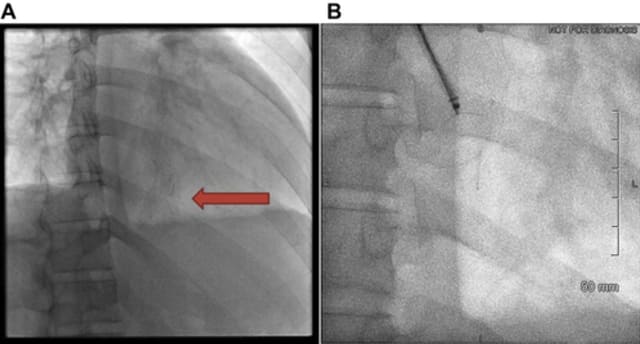

Die kanadischen Ärzte suchten weiter nach der Ursache für die Herzbeutelentzündung, wie die medizinische Zeitung den Fallbericht der «Journals of the American College of Cardiology» zitiert. Erst ein MRT und eine zusätzliche CT-Untersuchung zeigten zwei metallische Fragmente im rechten Ventrikelmyokard, die in die rechte Herzkammer hineinragten.

Dem 24-jährigen Mann wurden die beiden metallischen Nadelfragmente in der Folge über die rechte Vena jugularis mithilfe eines endovaskulären Systems entfernt. Die Fragmente waren neun und sieben Milimeter lang (siehe Bild). Nach zehn Monaten erholte sich der junge Patient vollständig.